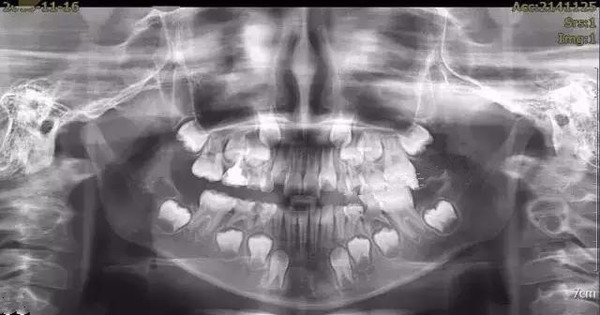

儿童面部x光 牙齿

儿童面部x光 牙齿,面部x光

牙齿的牙根是埋在牙槽骨中的 医生没有透视眼 为了解患牙的牙根的

牙片有两种,一种小小的,主要看局部牙齿的情况,片子出来只有1/8

患者牙齿x光片显示乳光牙随腔闭锁趋势

当然,正确的诊断必须通过牙齿模型和面部计量,但是在商谈室

小孩满脸都是牙齿

没换牙的小孩的x光图

小孩的头骨全是牙齿图

4岁儿童牙齿x光片

正常儿童牙齿x光图